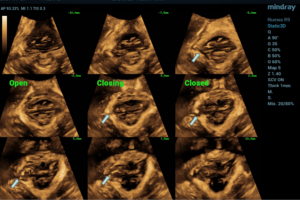

The intelligent measuring kit was used to measure the bilateral levator-urethral gap (LUG) (in contraction, the distance between the LAM and the midline of the urethra is 25 mm, which is the critical value for diagnosing LAM injury. For Asians, 23.4 mm can also be used as the critical value; during the Valsalva state, LHA <25 cm2, for Asians, refer to <20 cm2) (7-10) (Figure 4).

In contrast to the traditional 2D ultrasound method of directly observing LAM shape and attachment point continuity, the diagnosis method of LAM was first proposed by Dietz in 2005 (23). LAM injury was diagnosed by TUI mode under 3D conditions on the volume obtained during maximum contraction of the pelvic floor muscles. LAM avulsion was diagnosed when LAM discontinuity was present in at least three consecutive sections in TUI mode between the insertion of the puborectalis muscle and the attachment of the pubic ramus. Through the TUI pattern, it is possible to observe whether the LH is symmetrical or not, and it is also reasonable to infer LAM injury when both sides of the LH are asymmetrical (24). In most cases of LAM injury, qualitative evaluation can diagnose the presence or absence of LAM injury. However, in some cases, subjective perception alone is not sufficient to be comprehensive. Using TUI, LAM injury can be quantitatively assessed through two key metrics: (I) symmetry evaluation of the LH across sequential planes, and (II) measurement of the LUG, defined as the distance between the urethral center and the LAM insertion point on the pubic ramus. LAM avulsion was diagnosed when LUG exceeded 25 mm in three consecutive TUI planes. Due to the different pelvic sizes of women of different races, some studies have shown that the best LUG cut-off values for the diagnosis of LAM injury in Asian women are 23.65 and 23.05 mm (25). This study showed that the LUG of the forceps group, the non-forceps group, and the elective cesarean section group decreased in turn in the state of anal contraction. The LHA of vaginal delivery (with and without forceps) by Valsalva was greater than that of elective cesarean section, which was consistent with the results of the above study, and showed that forceps had some effect on LAM injury.

Dietz et al. have suggested that when performing a maximum Valsalva maneuver, LHA reaching 25 cm2 is considered abnormally dilated (23). Due to the racial difference, the height and pelvic size of European and American women are larger than those of Asian women. Current studies suggest that when the LHA of Asian women is greater than 20 cm2, it is considered that the LH is overinflated and the LAM will be damaged. During labor, the pelvic floor muscles stretch and the LH expands to allow fetal delivery. Measurement of its area can effectively reflect the function of the levator muscle and the degree of pelvic floor structure relaxation. The smaller the measurement, the less pelvic floor relaxation and the lower the risk of PFD. Pregnancy itself is a precipitating factor for pelvic floor changes. Even women who have a cesarean section experience pelvic floor stretching and minor damage as a result of pregnancy (although usually less than during vaginal delivery). Epidemiological studies have shown that both pregnancy and delivery mode are independent risk factors for PFD. Previous studies have investigated the pelvic floor structure of women with vaginal delivery and elective cesarean delivery, and the results showed that the incidence of pelvic floor PFD in women with vaginal delivery was higher than that in women with cesarean delivery (26,27). This study measured LHA under Valsalva, and found that LHA in women with elective cesarean delivery was lower than that in those with vaginal delivery. Secondly, through data analysis, we found that there was no significant difference in the effect of vaginal delivery women using forceps or not on LHA. It further indicates that elective cesarean section may have a certain protective effect on pelvic floor structure compared with the other two delivery methods.